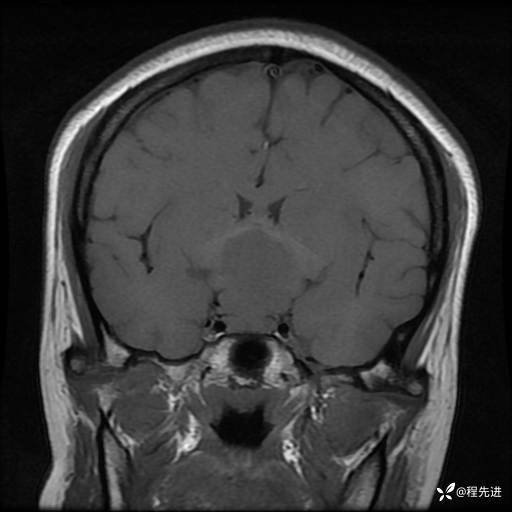

MRI平扫+增强:

T2: